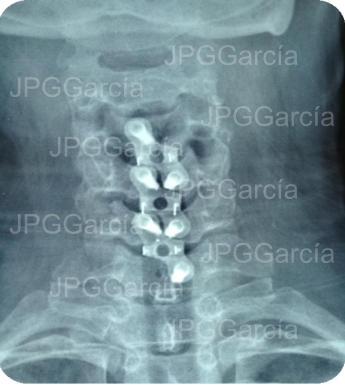

Extrusión discal cervical y tratamiento microquirúrgico

con colocación de cajas intersomáticas

Tratamiento neuroquirúrgico con colocación de cajas intersomáticas

cervicales hasta 3 niveles por vía anterior vistas anteroposterior y lateral

Tratamiento neuroquirúrgico

con colocación de cajas

intersomáticas cervicales hasta

3 niveles por vía anterior vistas

anteroposterior y lateral